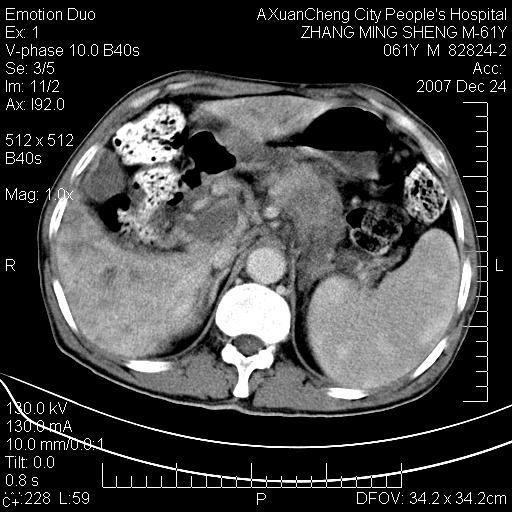

标题: CT11031:M61Y,胰腺占位

大家侃侃门静脉和胆管系统怎么回事,肝内转移?

1,肝硬化,脾大.

2,肝内多发结节状低密度占位,伴门脉及肠系膜上v栓子形成.考虑a;门脉及肠系膜上v血栓后肝改变.b;弥漫型肝癌伴门脉及肠系膜癌栓.

肝硬化,门脉高压,脾肿大;弥漫性肝癌,肝内、门脉、腹膜后淋巴结转移,肝内外胆管扩张,胰头区占位,建议mr检查

胰腺癌伴肝内转移;门脉、肠系膜上v癌栓形成。

考虑为:胰腺癌伴肝脏转移、腹膜后淋巴结转移,门静脉及肠系膜上静脉瘤栓形成。

胰体尾癌伴肝内转移,门静脉及肠系膜上静脉瘤栓形成.